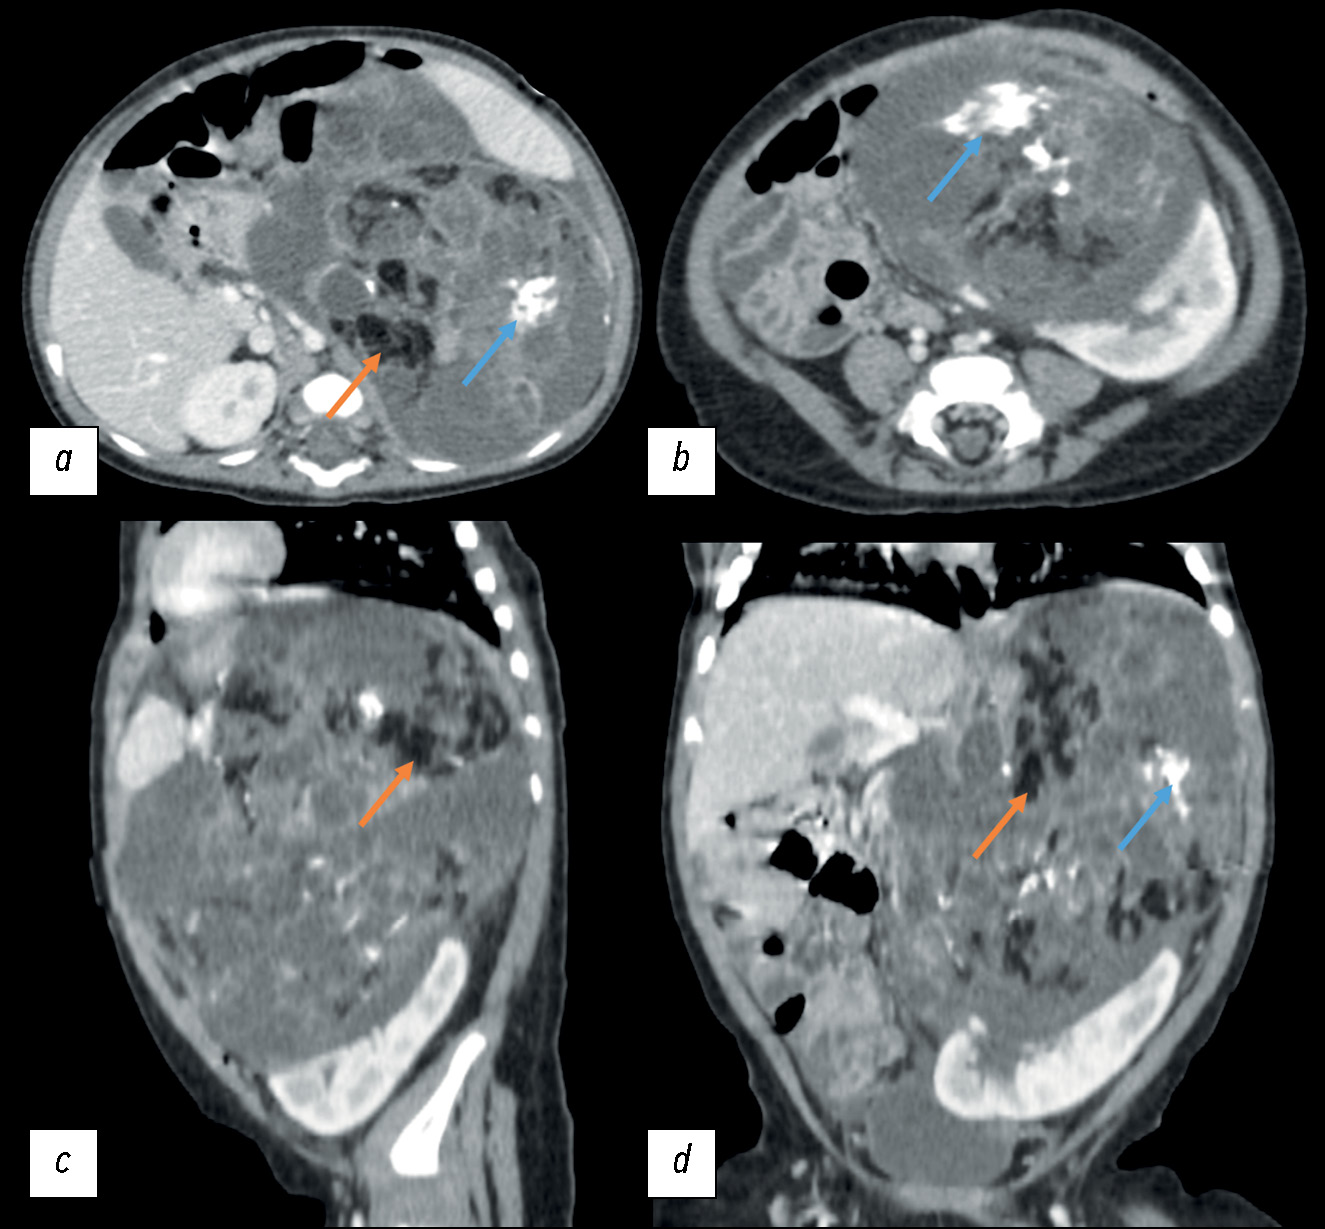

September 23, 2020: A contrast-enhanced abdominal multislice computed tomography (MSCT) revealed a retroperitoneal space-occupying mass on the left, measuring 81 × 71 × 87 mm (volume: 260 cm3), with a heterogeneous structure incorporating areas of calcification and inclusion cysts; the contrast uptake was weak. The neoplasm extended to the renal sinus area, without discernible signs of extension into the renal parenchyma. The adrenal gland extended across the lateral contour. The renal vessels on the left side followed the tumor contour; the superior mesenteric artery was displaced to the right, while the celiac artery was displaced upward (Fig. 1).

Fig. 1. Initial abdominal computed tomography using intravenous contrast dated September 23, 2020, a pattern of a space-occupying retroperitoneal mass on the left: (a) axial plane; the arrow indicates the displacement of the superior mesenteric artery to the right; (b) axial plane; (c) sagittal plane; the arrow indicates the upward displacement of the celiac artery; (d) coronal plane; the arrow indicates the tumor extension into the renal sinus.

The following day, abdominal computed tomography was conducted, which verified calcification and fat deposits in the mass with the cystic and solid components, with a weak contrast uptake (Fig. 5).

Fig. 5. Contrast-enhanced abdominal computed tomography dated November 1, 2020: (a, b) axial plane; (c) sagittal plane; (d) coronal plane. Orange arrows indicate the hypodense areas (fat deposits) of the tumor, with a density of –80 HU; blue arrows indicate calcification.